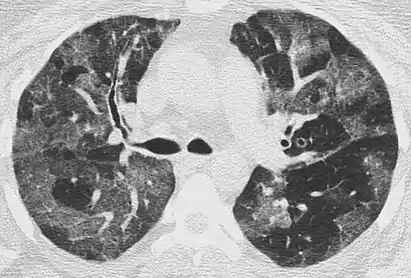

CT image showing diffuse GGOs throughout both lungs. An abscess is also noted in the right lung (screen left). - Adenocarcinoma in situ of the lung

Diffuse

The diffuse pattern typically refers to GGOs in multiple lobes of one or both lungs. Broadly, a diffuse pattern of GGO can be caused by displacement of air with fluid, inflammatory debris, or fibrosis. Cardiogenic pulmonary edema and ARDS are common causes of a fluid-filled lung. Diffuse alveolar hemorrhage is a rarer cause of diffuse GGO seen in some types of vasculitis, autoimmune conditions, and bleeding disorders.[6]

Inflammation and fibrosis can also cause diffuse GGOs. Pneumocystis pneumonia, an infection typically seen in immunocompromised (e.g. patients with AIDS) or immunosuppressed individuals, is a classic cause of diffuse GGOs. Many viral pneumonias and idiopathic interstitial pneumonias can also lead to a diffuse GGO pattern. Radiation pneumonitis, a side effect of pulmonary radiation therapy, can lead to pulmonary fibrosis and diffuse GGOs.[6]